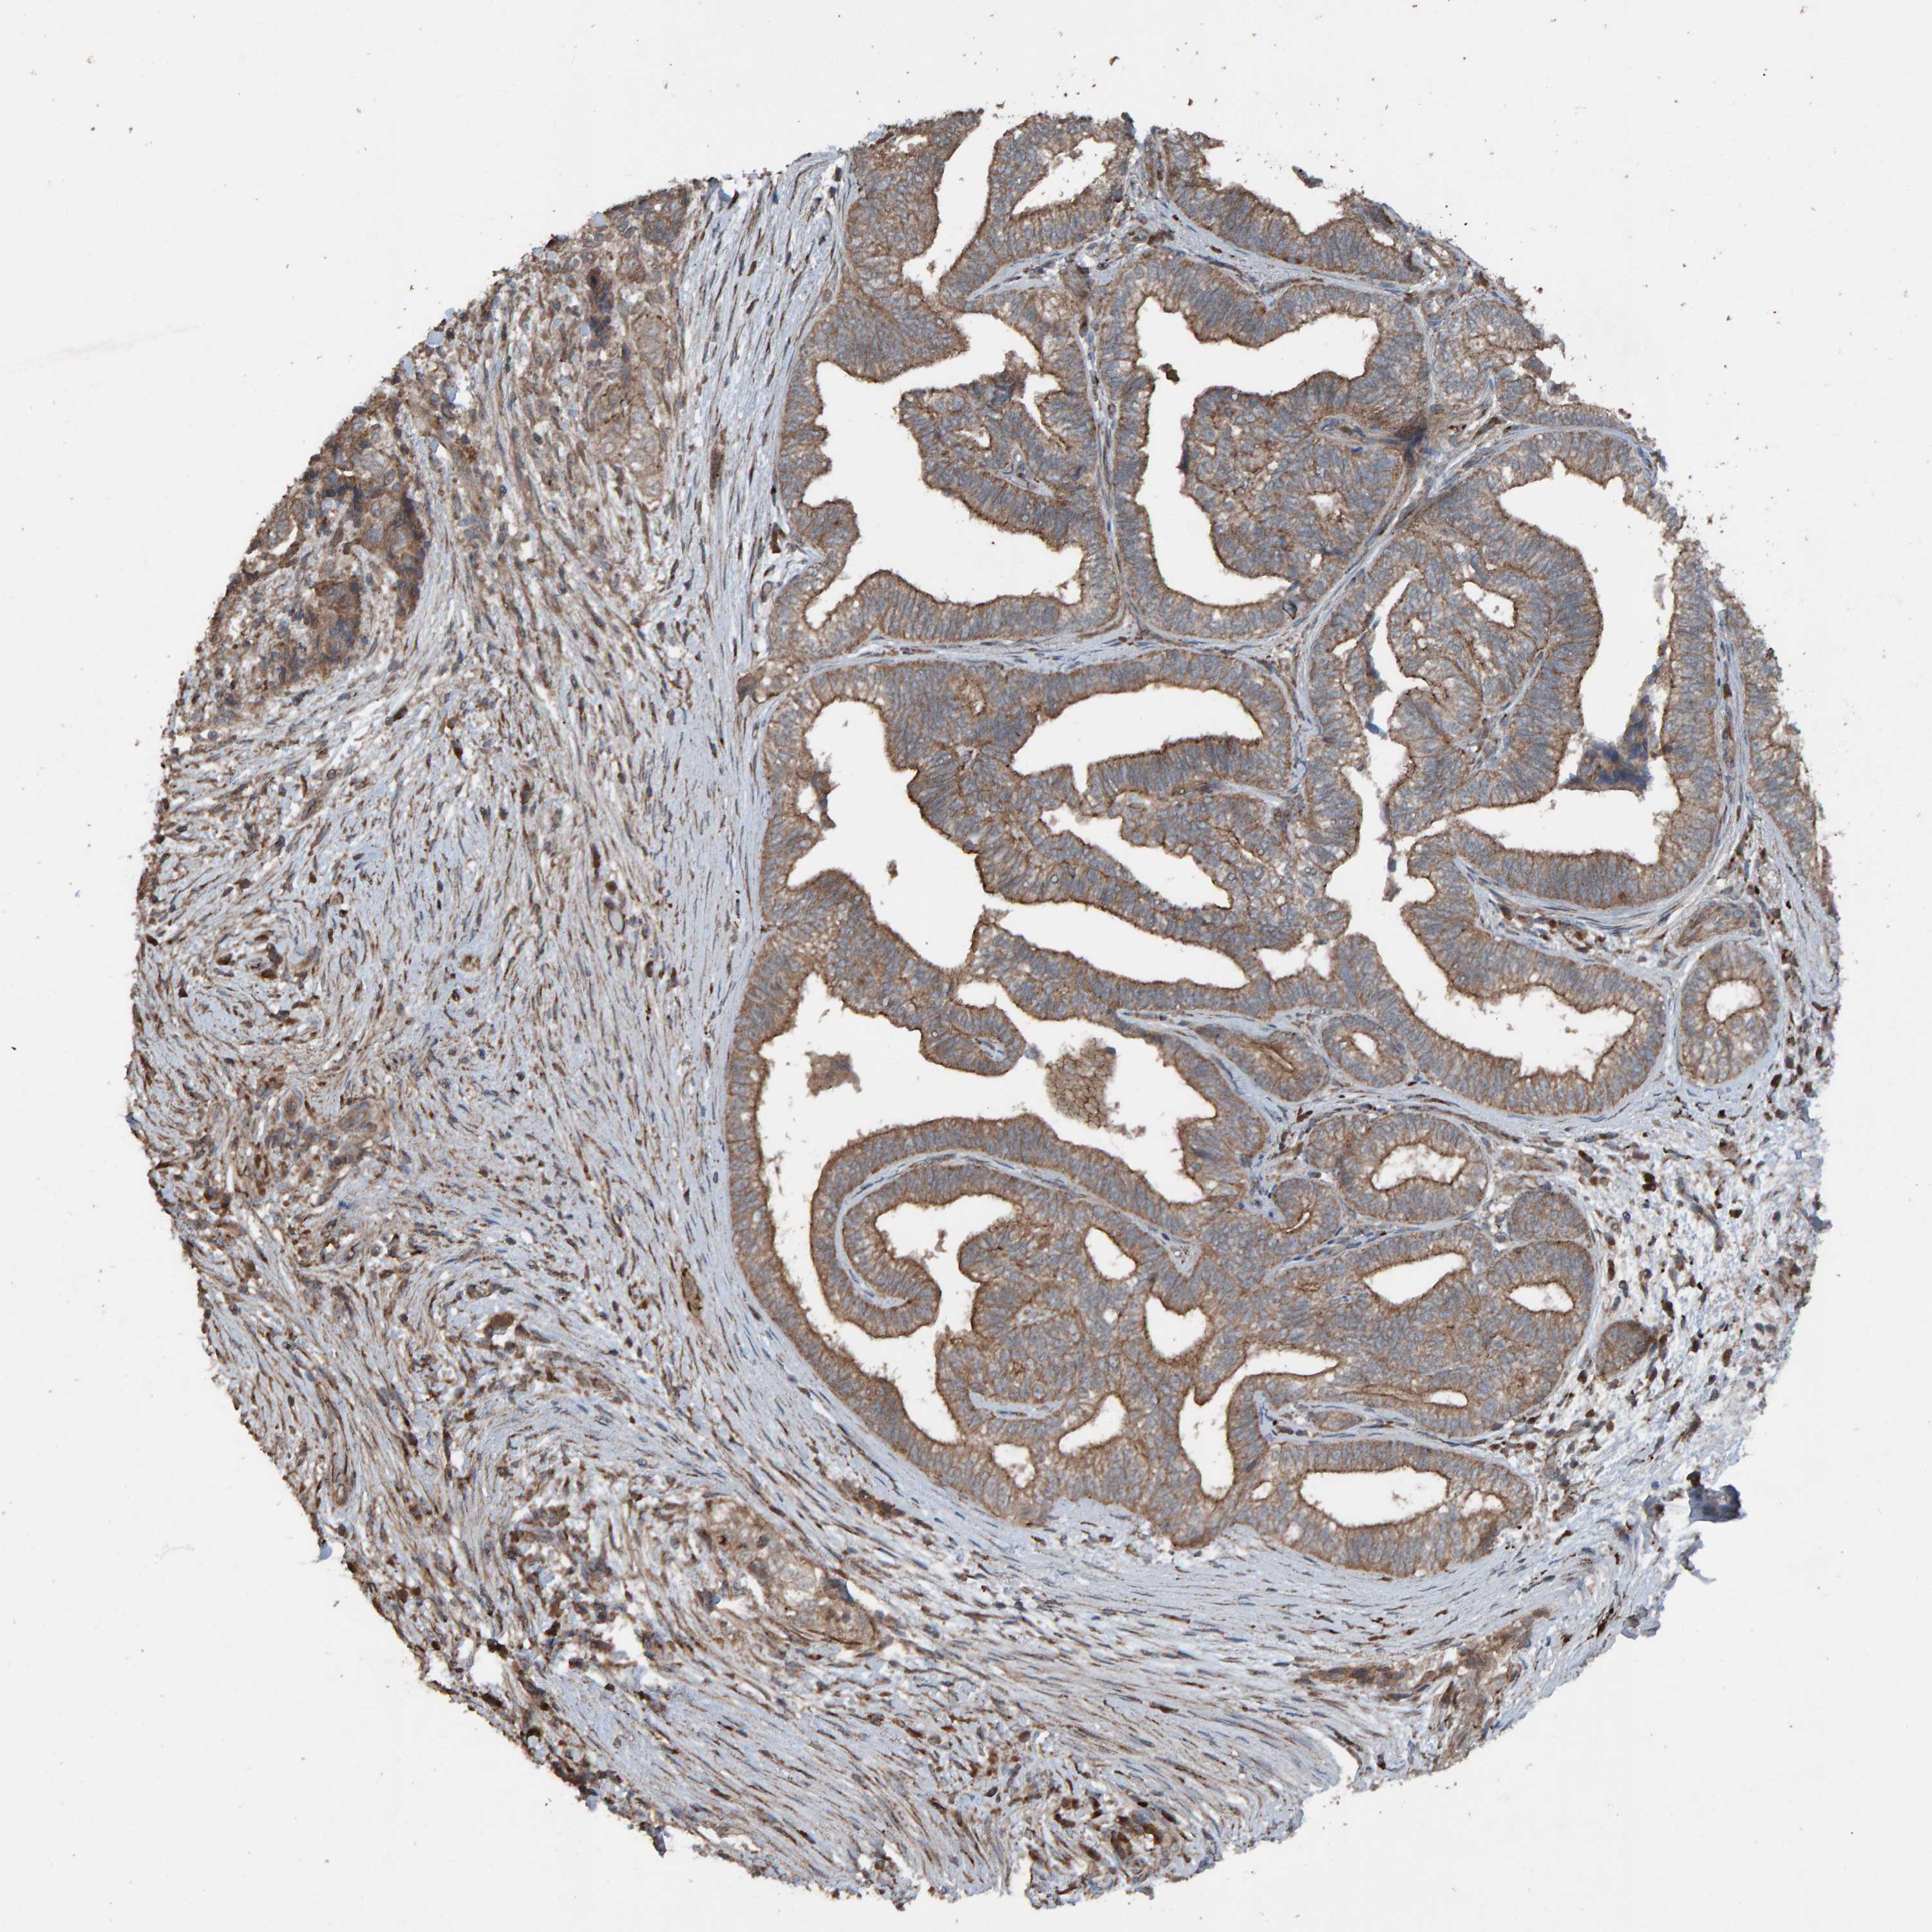

PANCREATIC CANCER - Protein expressioni

A mouse-over function shows sample information and annotation data. Click on an image to view it in a full screen mode. Samples can be filtered based on level of antibody staining by selecting one or several of the following categories: high, medium, low and not detected. The assay and annotation is described here.

Note that samples used for immunohistochemistry by the Human Protein Atlas do not correspond to samples in the TCGA dataset.

Antibody stainingi

Antibody staining in the annotated cell types in the current human tissue is reported as not detected, low, medium, or high, based on conventional immunohistochemistry profiling in selected tissues. This score is based on the combination of the staining intensity and fraction of stained cells.

Each image is clickable and will lead to virtual microscopy that enables deeper exploration of all samples and also displays staining intensity scores, fraction scores and subcellular localization as well as patient and tissue information for each sample.

Antibody HPA023384

Staining

High

Medium

Low

Not detected

Intensity

Strong

Moderate

Weak

Negative

Quantity

>75%

75%-25%

<25%

None

Location

Nuclear

Cytoplasmic/membranous

Cytoplasmic/membranous,nuclear

Adenocarcinoma, NOS